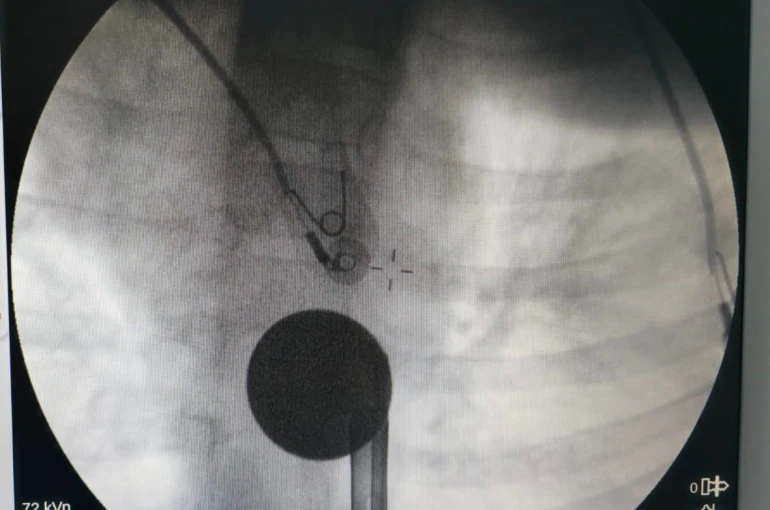

Yabancı cisim yutma şikayetiyle ailesi tarafından Siirt Eğitim ve Araştırma Hastanesine getirilen 8 yaşındaki Y.K., yapılan ilk değerlendirme ve görüntüleme tetkiklerinin ardından ilgili branşlarca operasyona alındı. Y.K.’nın yemek borusuna kadar ilerlediği tespit edilen madeni para, gastroenteroloji uzmanı Dr. Yaren Dirik ve kulak burun boğaz hekimi Yasin Gökçınar tarafından müdahale edilerek çıkartıldı. Operasyonun ardından bir süre gözlem altında tutulan Y.K., tedavisinin tamamlanmasıyla taburcu edildi.

Siirt Eğitim ve Araştırma Hastanesi Başhekim Yardımcısı Uzman Dr. Burak Özkan, çocuk hastalarda yabancı cisim yutma vakalarının ciddi riskler oluşturabileceğini söyledi. Uzm. Dr. Özkan, "Hastanemize başvuran 8 yaşındaki hastamızın yemek borusuna kaçan madeni para, gastroenteroloji ve KBB ekiplerimizin koordineli ve titiz çalışmasıyla herhangi bir komplikasyona yol açmadan başarılı bir şekilde çıkarılmıştır. Operasyon süreci sorunsuz geçmiş olup hastamızın genel durumu iyidir" dedi.